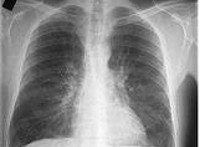

J42 Хронический бронхит неуточненный